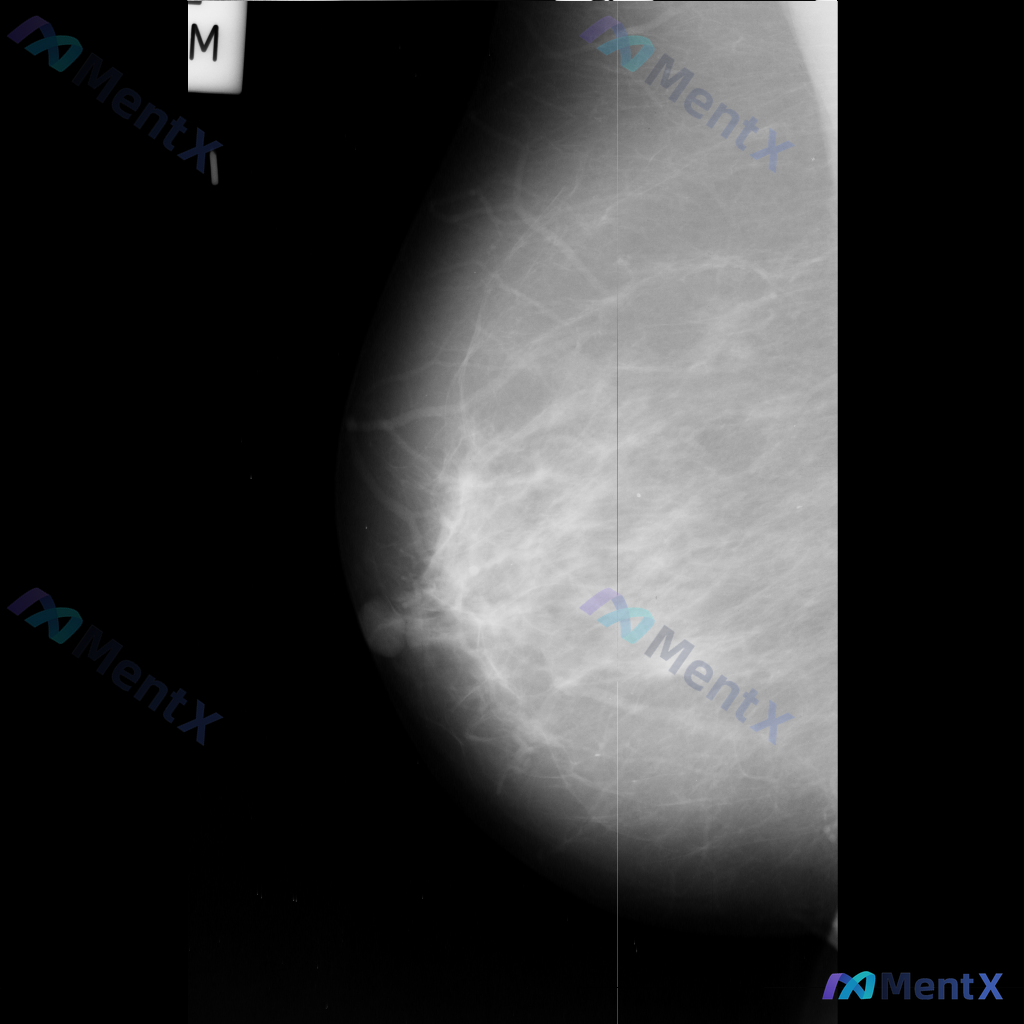

整理到一份乳腺钼靶影像资料,主要异常表现如下: - 部位:乳腺中部偏下方 - 影像征象:局灶性不规则腺体密度增高,伴结构扭曲 - 背景:致密型乳腺 目前仅单张影像资料,未提供其他体位、超声或临床病史。 想和大家讨论一下:单看这组异常表现,你会先往哪个方向考虑?后续如果要进一步明确,你觉得优先做什么检...

整理到一组乳腺钼靶影像的资料,分享给大家讨论: - 背景:不均匀致密型乳腺(BI-RADS C类) - 主要异常: 1. 乳腺下象限靠近乳头乳晕区,见两个大小不一的圆形/卵圆形高密度影,还有一个较小的类圆形高密度影,密度高于周围腺体,边缘相对清晰但略显模糊; 2. 上述高密度影周围的乳腺下象限,腺体...